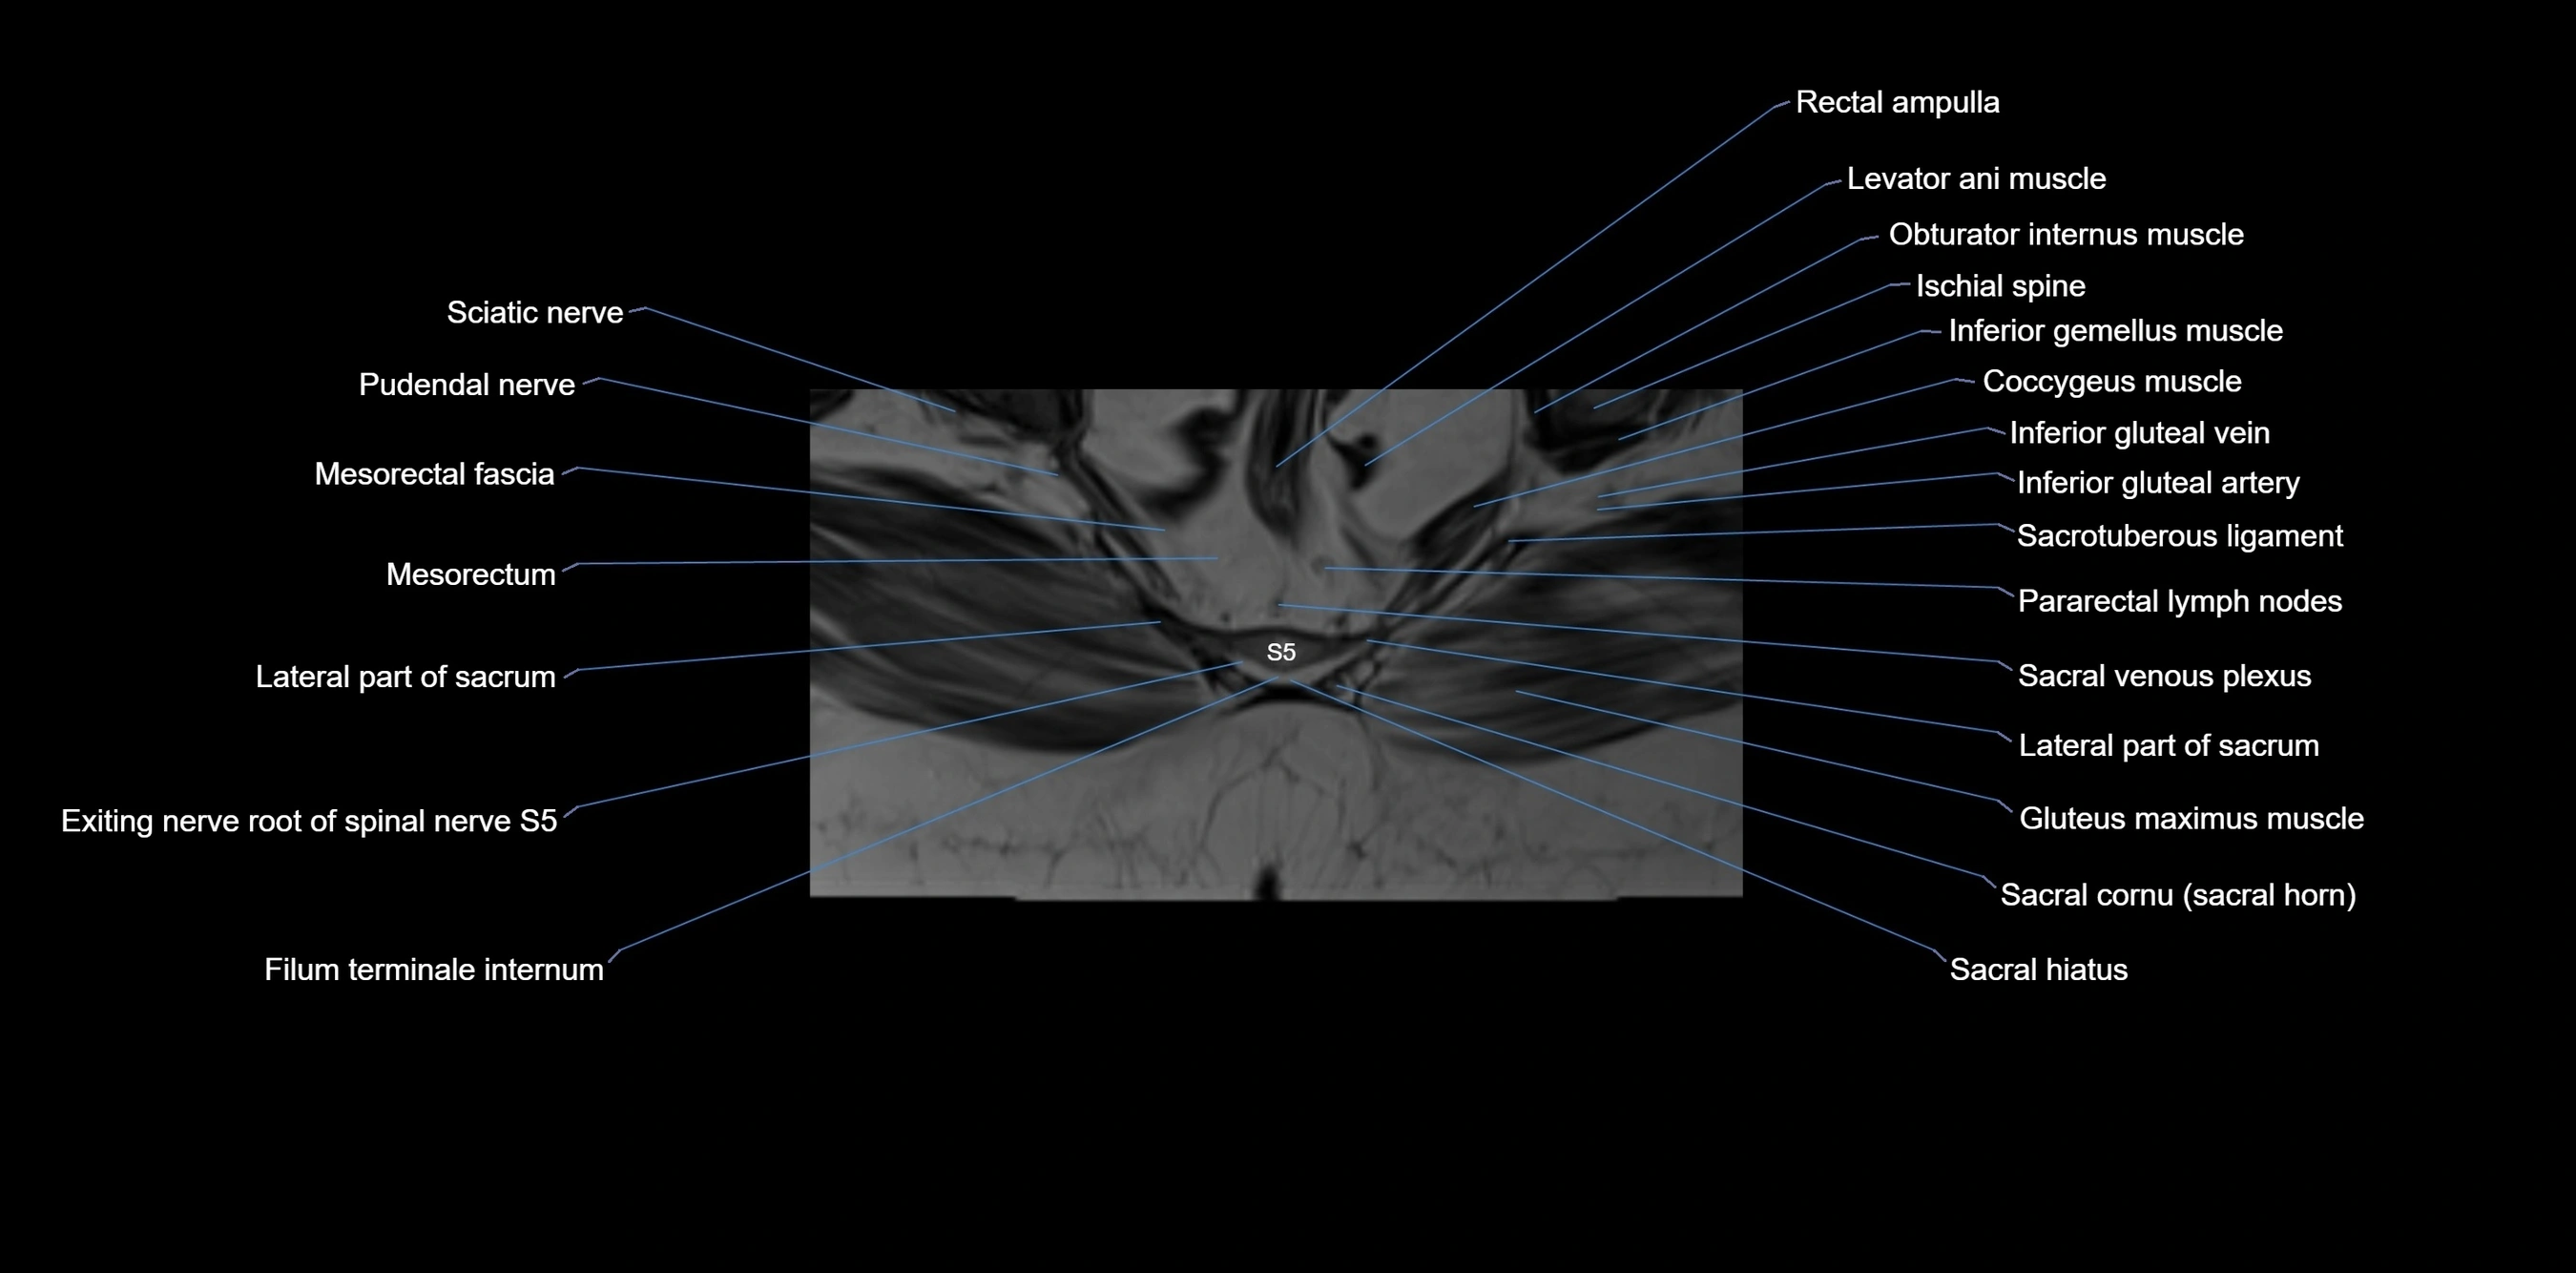

MRI Appearance

T1-weighted images:

• Cortical bone appears very low signal (dark); marrow shows intermediate signal

• Iliac fossa fat is bright against low-signal cortex

T2-weighted images:

• Cortical bone remains dark

• Marrow signal varies depending on fat content; edema or tumor shows hyperintensity

STIR:

• Suppresses fat, making bone marrow edema, fractures, or infiltrative lesions appear bright

• Excellent for trauma, sacroiliitis, and metastatic evaluation

T1 Fat-Saturated (Pre-contrast):

• Marrow: intermediate signal, fat suppressed

• Useful for detecting subtle marrow abnormalities adjacent to iliac cortex

T1 Fat-Saturated Post-Contrast (Gadolinium):

• Enhances vascularized structures, marrow pathology, tumors, and inflammatory changes

• Highlights soft tissue or bone invasion in pelvic neoplasms

MRI Non-Contrast 3D Imaging:

• Provides 3D morphology of iliac wing, crest, and articulations

• Used in preoperative planning for pelvic surgery and trauma reconstruction